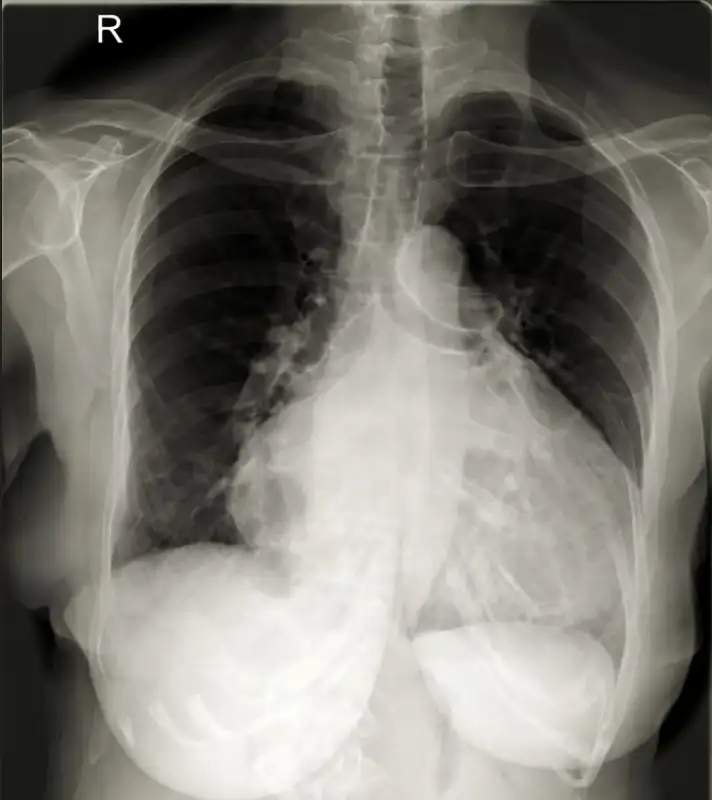

1. Rontgen dada (chest X-ray), menunjukkan ukuran jantung yang membesar sebagai temuan awal.